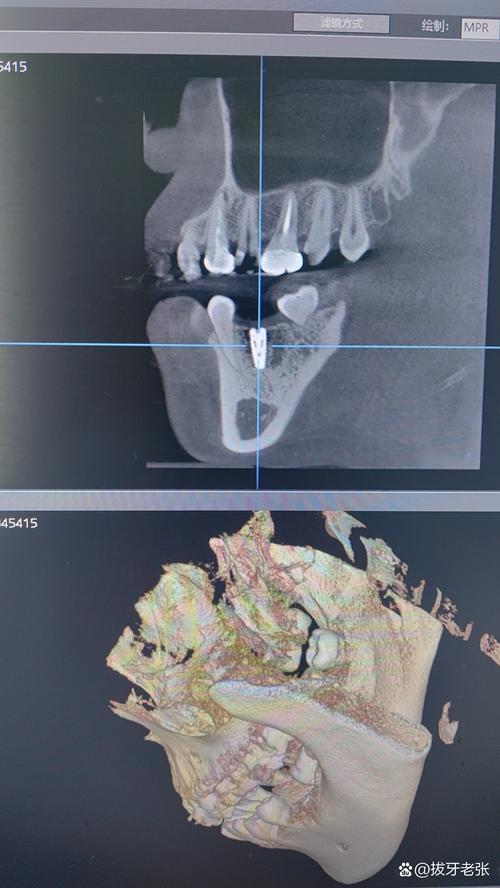

- 图像后处理:医生需通过专业软件(如Dexis、OnDemand)进行三维重建,多平面观察(MPR、CPR)、测量骨量、模拟种植体植入路径,确保方案可行性。